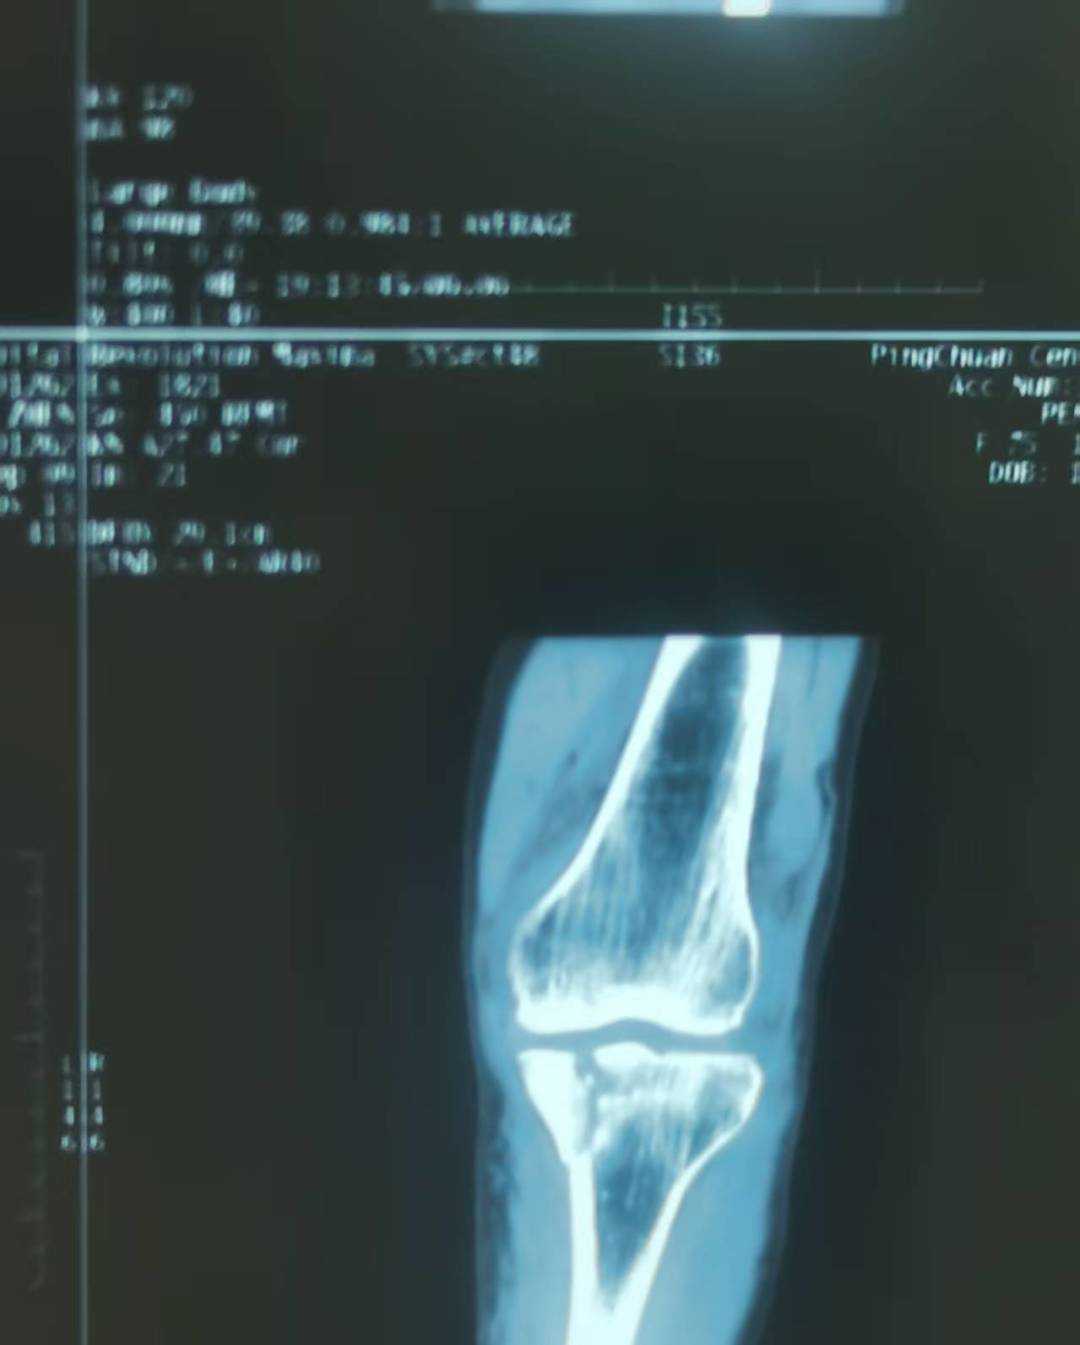

近日,75岁的彭女士因“外伤致左膝部肿痛伴活动受限4小时余”在平川中心卫生院入院。经细致检查,诊断为“左侧胫骨内侧平台粉碎性骨折;左侧股骨内髁撕脱性骨折;左膝关节积液。”主管医生常磊立即给予消肿、止痛等对症支持治疗,并为其制定了详细的治疗方案,同时向患者及其家属详细阐述了病情及治疗计划,患者及其家属一致同意择期进行手术治疗。

11月16日,外科组织开展术前讨论,邀请县级骨科专家主治医师陈龙潭和平川中心卫生院副主任医师杞向军参加。结合彭女士的具体病情,专家们从手术指征、手术方式等多个方面进行了全面分析,最终决定采用左胫骨平台近端内侧解剖锁定T型钢板植入固定+植骨方案,并确定了手术时间。

11月17日上午,外科医生会同县医院下沉的骨科专家陈龙潭,成功为患者施行左侧胫骨平台骨折切开复位内固定术+开窗骨移植术。术后,彭女士恢复状况良好,其本人及家属对手术效果极为满意,且为能在家门口获得县级专家的诊疗深感触动。